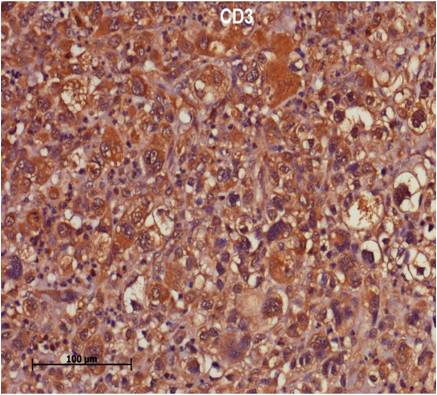

Immunohistochemistry Beauties

Lymphoma Panel in Humans

Soft Tissue Panel in Humans

We caters to clients looking for solutions by Immunohistochemistry (IHC) Diagnosis. We conduct IHC for routine and novel antibodies both for research and Diagnostics.